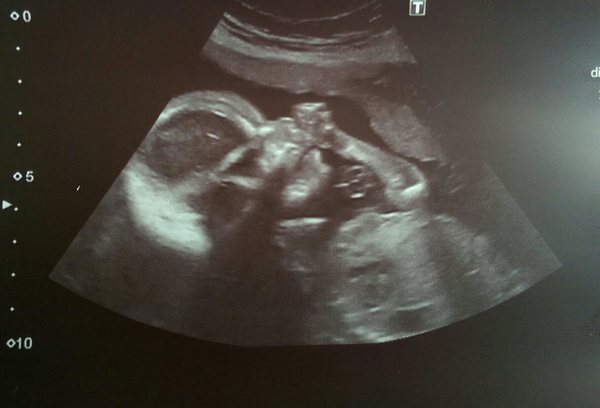

BUT had my 20 week scan today and little nibling was happy, healthy and moving about ALL OVER THE PLACE!!

Even the sonographer was chuckling when bub started kicking it's legs over its head, gorgeous! And got an hilarious pic of it! Anyhoo treacle I hope this may offer reassurance. Sonographer was completely nonplussed and unsurprised that I'd felt nothing and said it could still be a few weeks til I feel the nonstop movements of nibling! Phewf! Jessica, I'll be in contact for that coffee soon